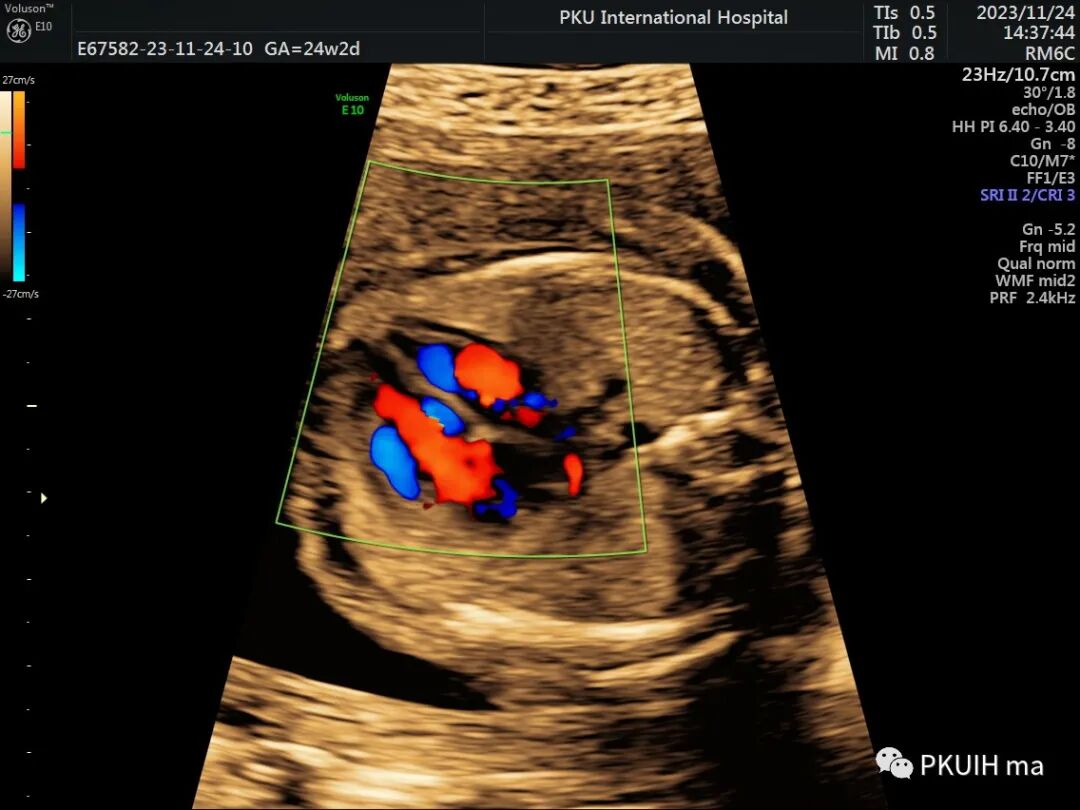

最后可借助于CDFI,CoA胎儿主动脉峡部出现持续性血流信号,当出现湍流时,CoA发生风险明显增加。严重的峡部可出现反向血流灌注。